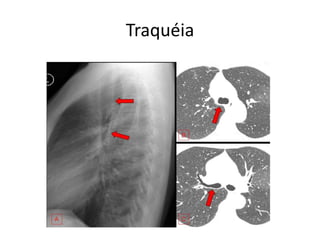

Traquéia